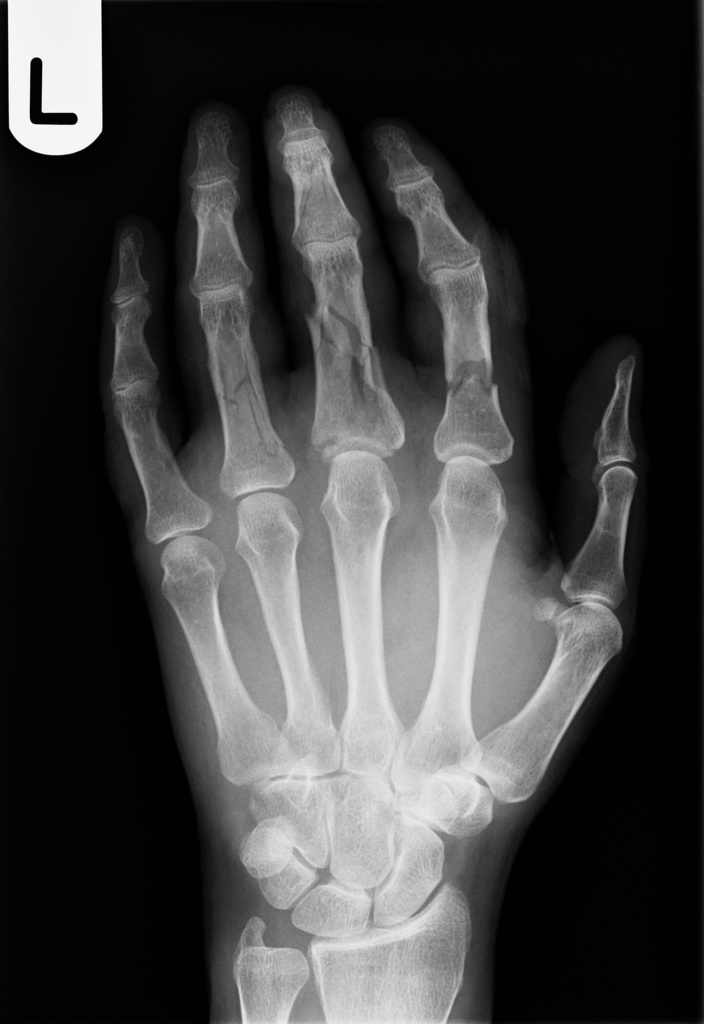

php Fracture detection in hand using image proccessing Stack Overflow Crushing Injury Finger Tip A nail bed injury almost. Crush injuries of the hand involve damage to multiple structures within the hand, loss of tissue, devascularisation and possibly amputation of. If just skin is removed from the finger tip or if there is just a little bit of bone exposed at the finger tip, this injury can be treated with a simple dressing. It. Crushing Injury Finger Tip.